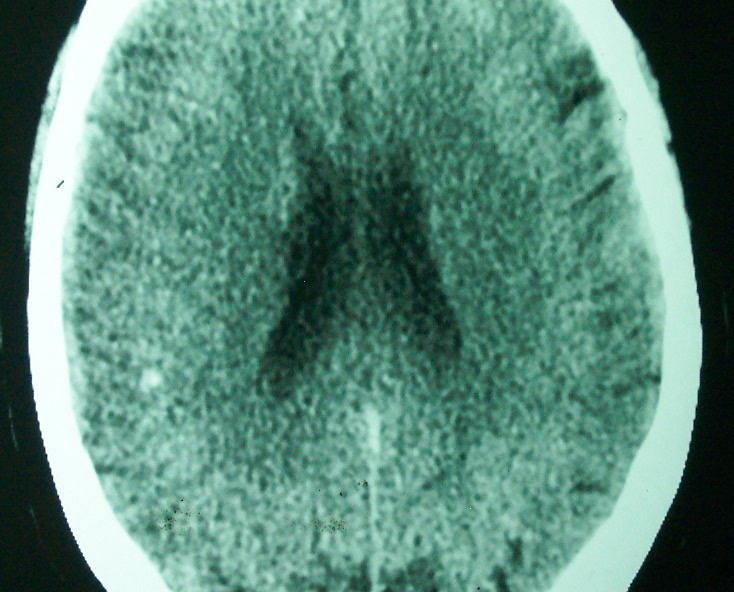

标题: CT18022:颅内多发稍高密度影 [打印本页]

标题: CT18022:颅内多发稍高密度影

f     60    左侧肢体活动无力3天余,    神志情,  无抽搐史   无发热   否认囊虫接触史

有囊有节有钙化,这个表现符合混合型脑囊虫病.请结合临床资料并进行补体结合试验.

有囊有节有钙化,考虑混合型脑囊虫病.